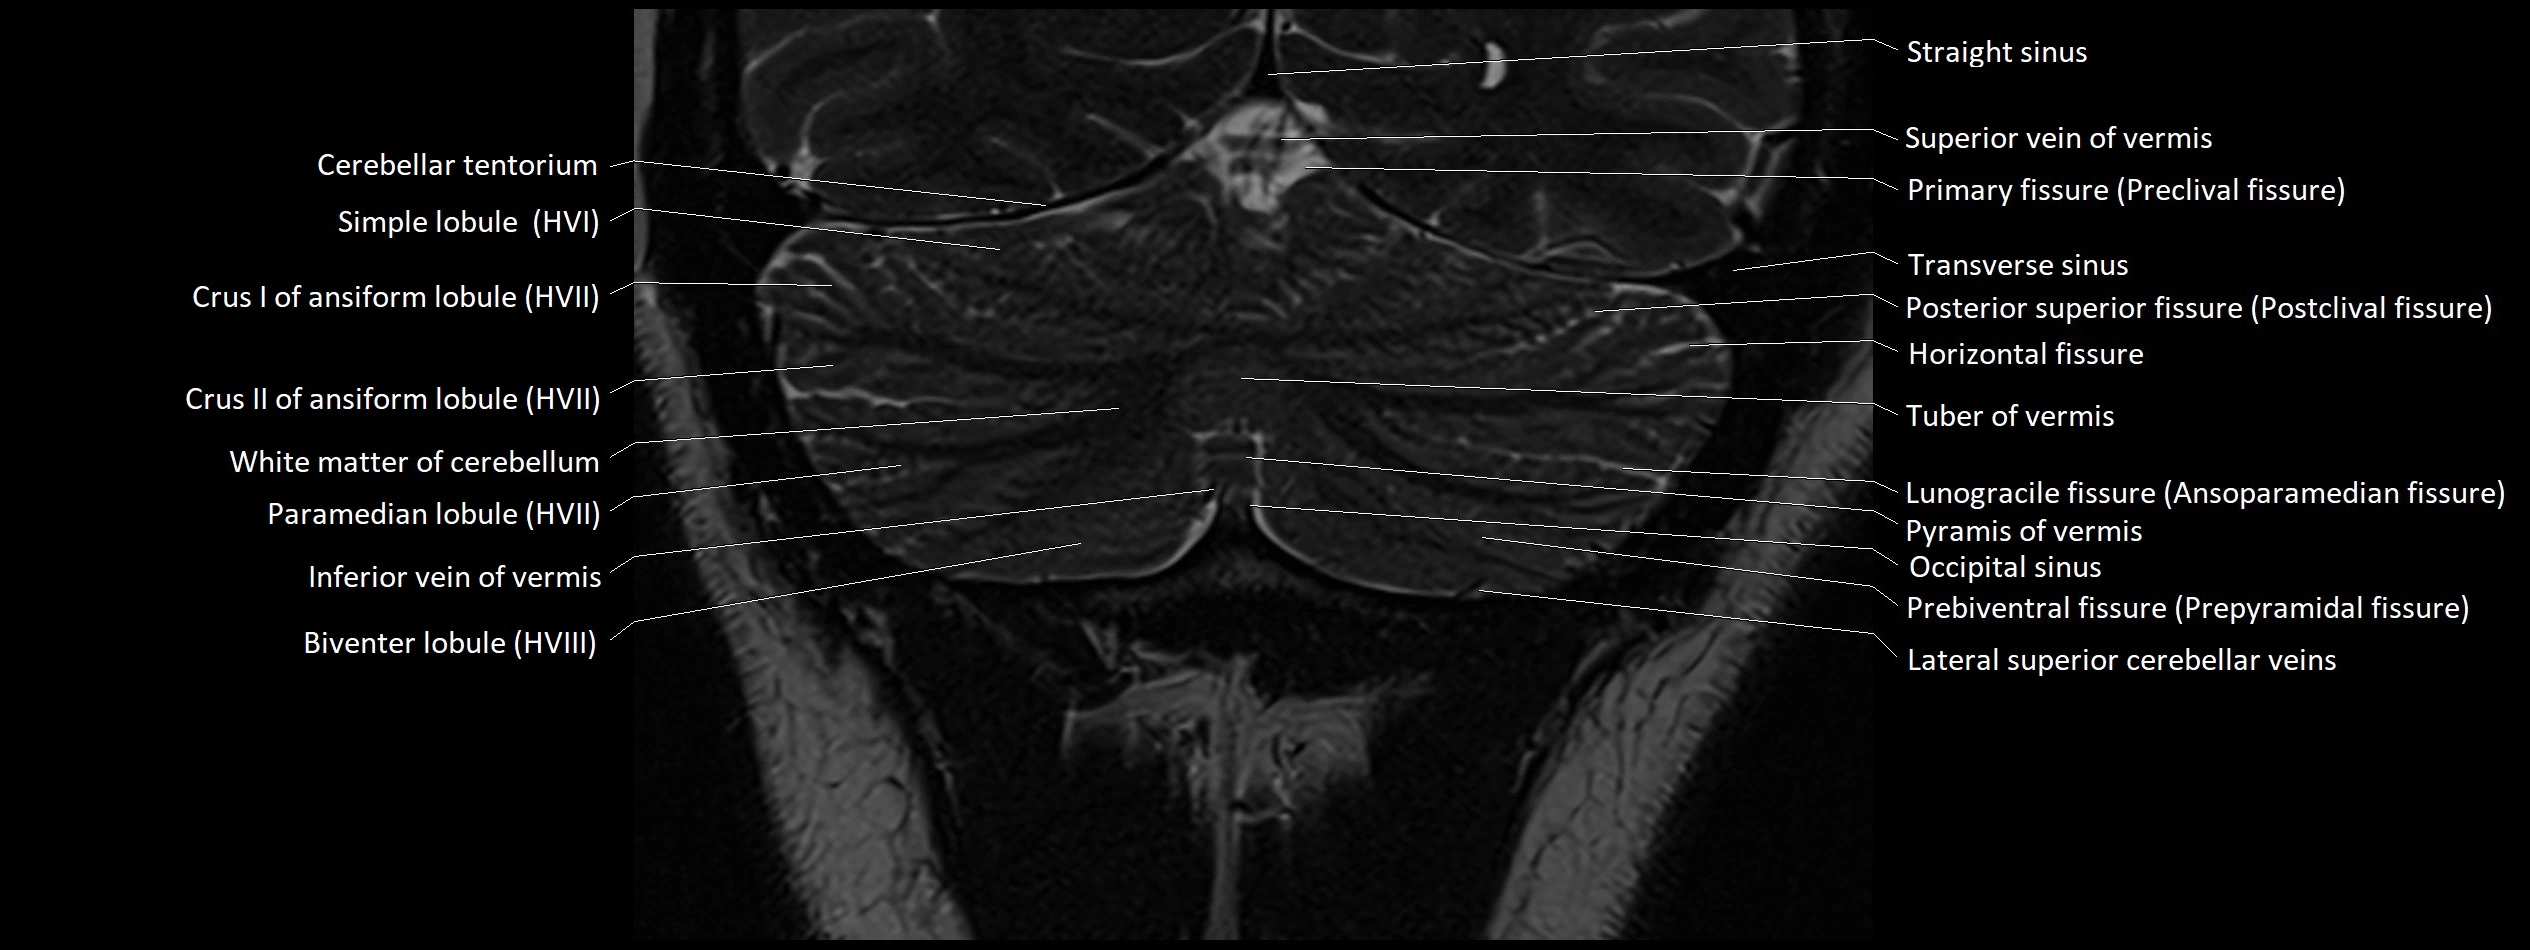

MRI images